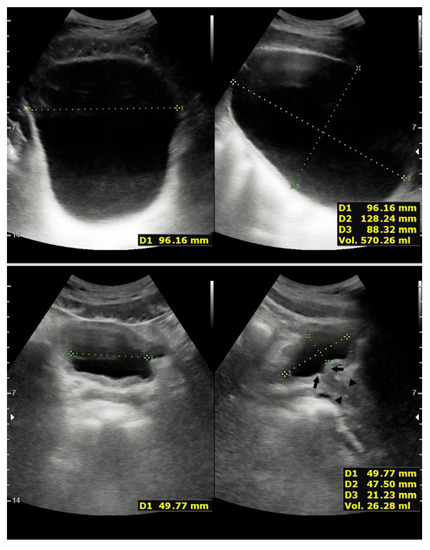

2.3. Case 3